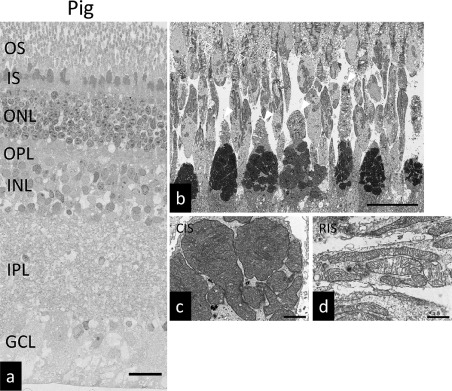

以前报道过猪视网膜含有巨线粒体。由于哺乳动物光感受器细胞中存在巨线粒体的报道很少,我们用扫描电子显微镜(SEM)评估了猪、兔和小鼠的视网膜形态。为了获得宽视场的高分辨率图像,我们采用了独特的扫描电镜方法。在传统的SEM中,不需要嵌入和切片步骤,而仅查看标本的表面。相反,我们的SEM技术包括将单个或连续的超薄切片安装在载玻片上,被重金属染色以及扫描反向散射的电子。通过数字化“缝合”连续的SEM图像,可以以高分辨率获得宽视场图像。图1a显示了猪视网膜的电镜图像。图1b为猪光感受器细胞层的电镜图像。图1c为图1a中视锥节的放大图,图1d为图1a中视杆节的放大图,图2a为兔视网膜的电镜图像。图2b为兔光感受器细胞层的电镜图像。图2c显示了图2a中视锥节的放大视图。图2d显示了图2a中的视杆节的放大视图。图3a显示了小鼠视网膜的电子显微镜图像。图3b所示为小鼠感光细胞层的电镜图像。图3c示出了图3a中的视锥节的放大图。 图3d示出了图3a中视杆节的放大图。OS:外节,IS:内节,ONL:外核层,OPL:外丛状层,INL:内核层,IPL:内丛状层,GCL:神经节细胞层。 CIS:视锥光感受器节。 RIS:视杆感光器节。

图1.猪视网膜的超微结构。